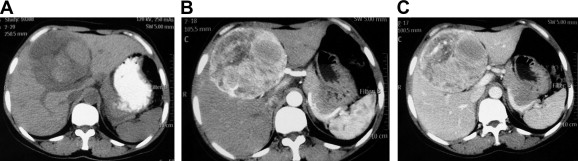

All patients received ultrasonography and computed tomography (CT) examinations, but only two patients received magnetic resonance imaging (MRI). On sonography, the tumors were seen as a hyperechoic mass, either homogeneous or heterogeneous. The lesions exhibited well-demarcated mass with heterogeneous density in plain CT scan. In arterial CT, the lesions were heterogeneously enhanced. In the portal venous phase, the lesions returned to an isoattenuating state (Fig. 1). In a 37-year-old woman complicated with renal PEComa, MRI showed heterogeneous hypointensity on T1-weighted images (T1WIs) and hyperintensity on T2-weigthed images (T2WI). After fat saturation, hyperintensity on T2WI in the liver lesion remained, but T2WI in the renal lesion showed hypointensity. In enhanced scanning, the lesions showed asymmetrical enhancement in arterial phase images (Fig. 2). In a 52-year-old woman with multiple liver lesions, MRI showed a lesion located on the left lobe and S8 of the liver. The lesions showed heterogeneous hypointensity on T1WI and heterogeneous hyperintensity on T2WI. After fat saturation, hyperintensity on T2WI remained. In enhanced scanning, the lesions showed asymmetrical enhancement in arterial phase images (Fig. 3). Prior to operation, one case was diagnosed with hepatic PEComa, three cases with hepatocellular carcinoma, and one case with hepatic adenomata.

MR image of hepatic PEComa (arrows) complicated with renal PEComa (arrow heads) ...

Figure 2.

MR image of hepatic PEComa (arrows) complicated with renal PEComa (arrow heads) in a 37-year-old woman. (A) T1-weighted MR image showed a heterogeneous hypointense mass with well-demarcated tumor margins. (B) T2-weighted MR image showed the same lesions with heterogeneous hyperintensity. (C) T2-weighted fat-suppressed MR image showed moderately heterogeneous hyperintensity in the liver lesion and moderate hypointensity in the renal lesion. (D) During the hepatic arterial phase, the lesions showed asymmetrical enhancement. MR = magnetic resonance; PEComa = perivascular epithelioid cell tumor.